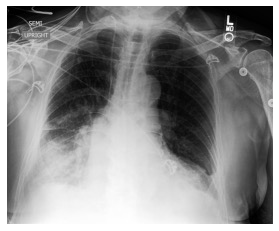

Automated diagnosis prediction from medical images is a valuable resource to support clinical decision-making. However, such systems usually need to be trained on large amounts of annotated data, which often is scarce in the medical domain. Zero-shot methods address this challenge by allowing a flexible adaption to new settings with different clinical findings without relying on labeled data. Further, to integrate automated diagnosis in the clinical workflow, methods should be transparent and explainable, increasing medical professionals' trust and facilitating correctness verification. In this work, we introduce Xplainer, a novel framework for explainable zero-shot diagnosis in the clinical setting. Xplainer adapts the classification-by-description approach of contrastive vision-language models to the multi-label medical diagnosis task. Specifically, instead of directly predicting a diagnosis, we prompt the model to classify the existence of descriptive observations, which a radiologist would look for on an X-Ray scan, and use the descriptor probabilities to estimate the likelihood of a diagnosis. Our model is explainable by design, as the final diagnosis prediction is directly based on the prediction of the underlying descriptors. We evaluate Xplainer on two chest X-ray datasets, CheXpert and ChestX-ray14, and demonstrate its effectiveness in improving the performance and explainability of zero-shot diagnosis. Our results suggest that Xplainer provides a more detailed understanding of the decision-making process and can be a valuable tool for clinical diagnosis.